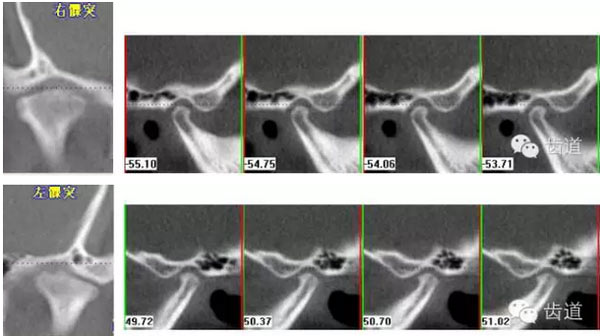

下頜后縮為主要特征的骨性II類,高角,前牙開(kāi)合,上前牙略唇傾,雙側(cè)下頜升支及髁狀突不對(duì)稱,右側(cè)較左側(cè)粗壯,左側(cè)髁狀突外斜面曾有吸收,但現(xiàn)骨白線與皮質(zhì)骨已比較連續(xù),上呼吸道正常。上

治療后關(guān)節(jié)截圖(CBCT)